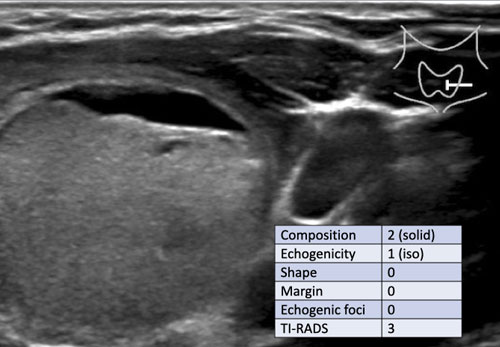

Trường hợp 2

Quan sát hình ảnh và xác định điểm TI-RADS.

Cuộn hình ảnh để xem điểm TI-RADS.